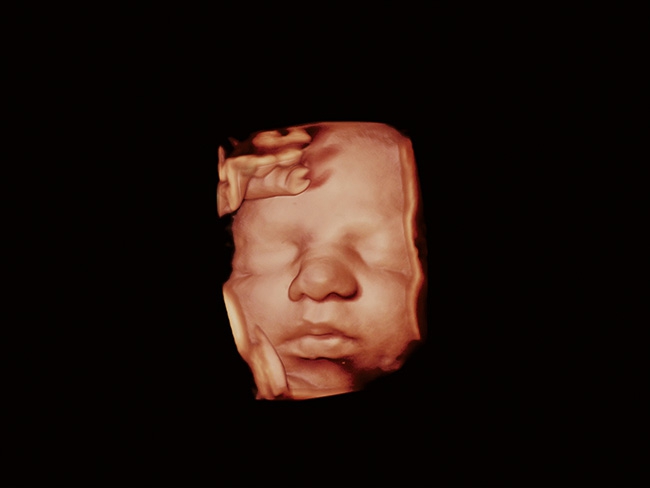

Aplio a550 может работать с линейным матричным датчиком и поддерживает новейшие монокристаллические датчики. Также Aplio a550 поддерживает большое количество дополнительных опций, таких как - SMI, Компрессионная эластография, Эластография сдвижной волны, Smart Fusion, исследования с использованием контраста (CEUS), 3D реконструкции в реальном времени (4D), функции автоматической оценки подвижности миокарда и фракции выброса.

• Fly Thru. Виртуальная эндосонография обеспечивает построение трехмерной модели полостей, протоков и сосудов в рельном времени, облегчает организацию инвазивных процедур и динамических исследований. Посредством Fly Thru можно установить шунты и стенты, проводить точные оперативные вмешательства.